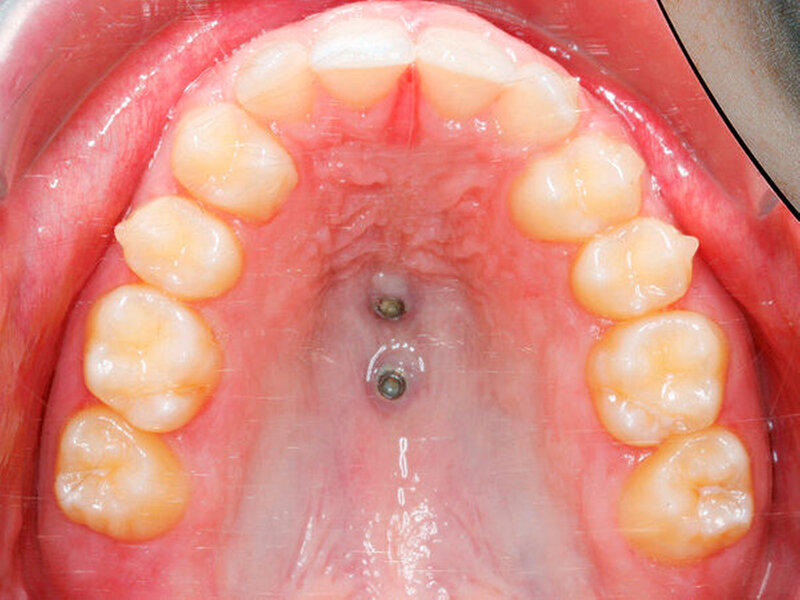

Das zweiphasige Vorgehen wird anhand eines 15-jährigen Patienten mit Aplasie beider oberer seitlicher Schneidezähne dargestellt (Abbildung 1). Die bleibenden oberen Eckzähne waren nach mesial gewandert, während die Milcheckzähne noch persistierten. Von Eltern und Patient wurde der kieferorthopädische Lückenschluss, möglichst mit Alignern, gewünscht. Die Behandlung begann mit dem Anpassen kieferorthopädischer Bänder auf den oberen ersten Molaren sowie der Insertion von zwei Mini-Implantaten (2 x 9 mm und 2 x 7 mm, Benefit, PSM) posterior der dritten Gaumenfalten in der sogenannten T-Zone [Becker, 2019; Wilmes, 2016]. Die Verbindung zu den Prämolaren wurde durch Gleitröhrchen (Tubes) und Klebeverbindungen mittels Composite realisiert (Abbildung 2, B-Mesialslider, [Wilmes, 2018]). Die Milcheckzähne wurden erst unmittelbar nach Einsetzen des Mesialsliders extrahiert, um die Geschwindigkeit des Lückenschusses zu erhöhen (Regional Accelatory Phenomenon – RAP [Verna, 2016]). Nach insgesamt zwölf Monaten sind alle Lücken nach mesial geschlossen (Abbildungen 3 und 4).